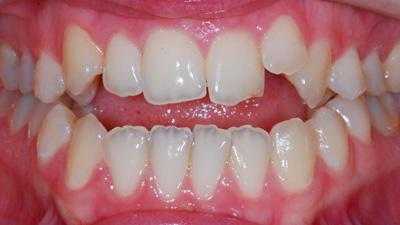

Внутриротовые признаки

В полости рта дистальный прикус определяется по выступающим вперед верхним фронтальным зубам. В норме, при ортогнатическом прикусе, верхние резцы перекрывают нижние примерно на 1/3. При дистальной патологии между верхними и нижними резцами образуется расстояние — «саггитальная щель».

Профиль до и после лечения дистального прикуса